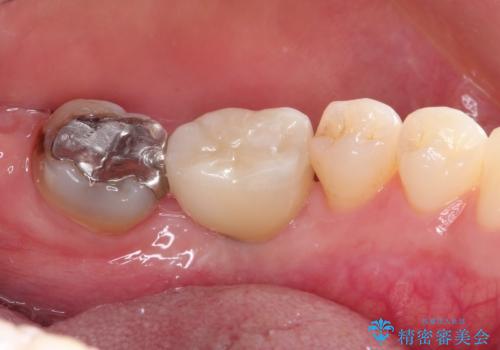

インプラントの種類:strauman SLActive

かぶせ物の種類:Bellezza screw retain

- Ⅲ度の分岐部病変をきたした第1大臼歯を抜去、待時しインプラントによる咬合回復を計画した。